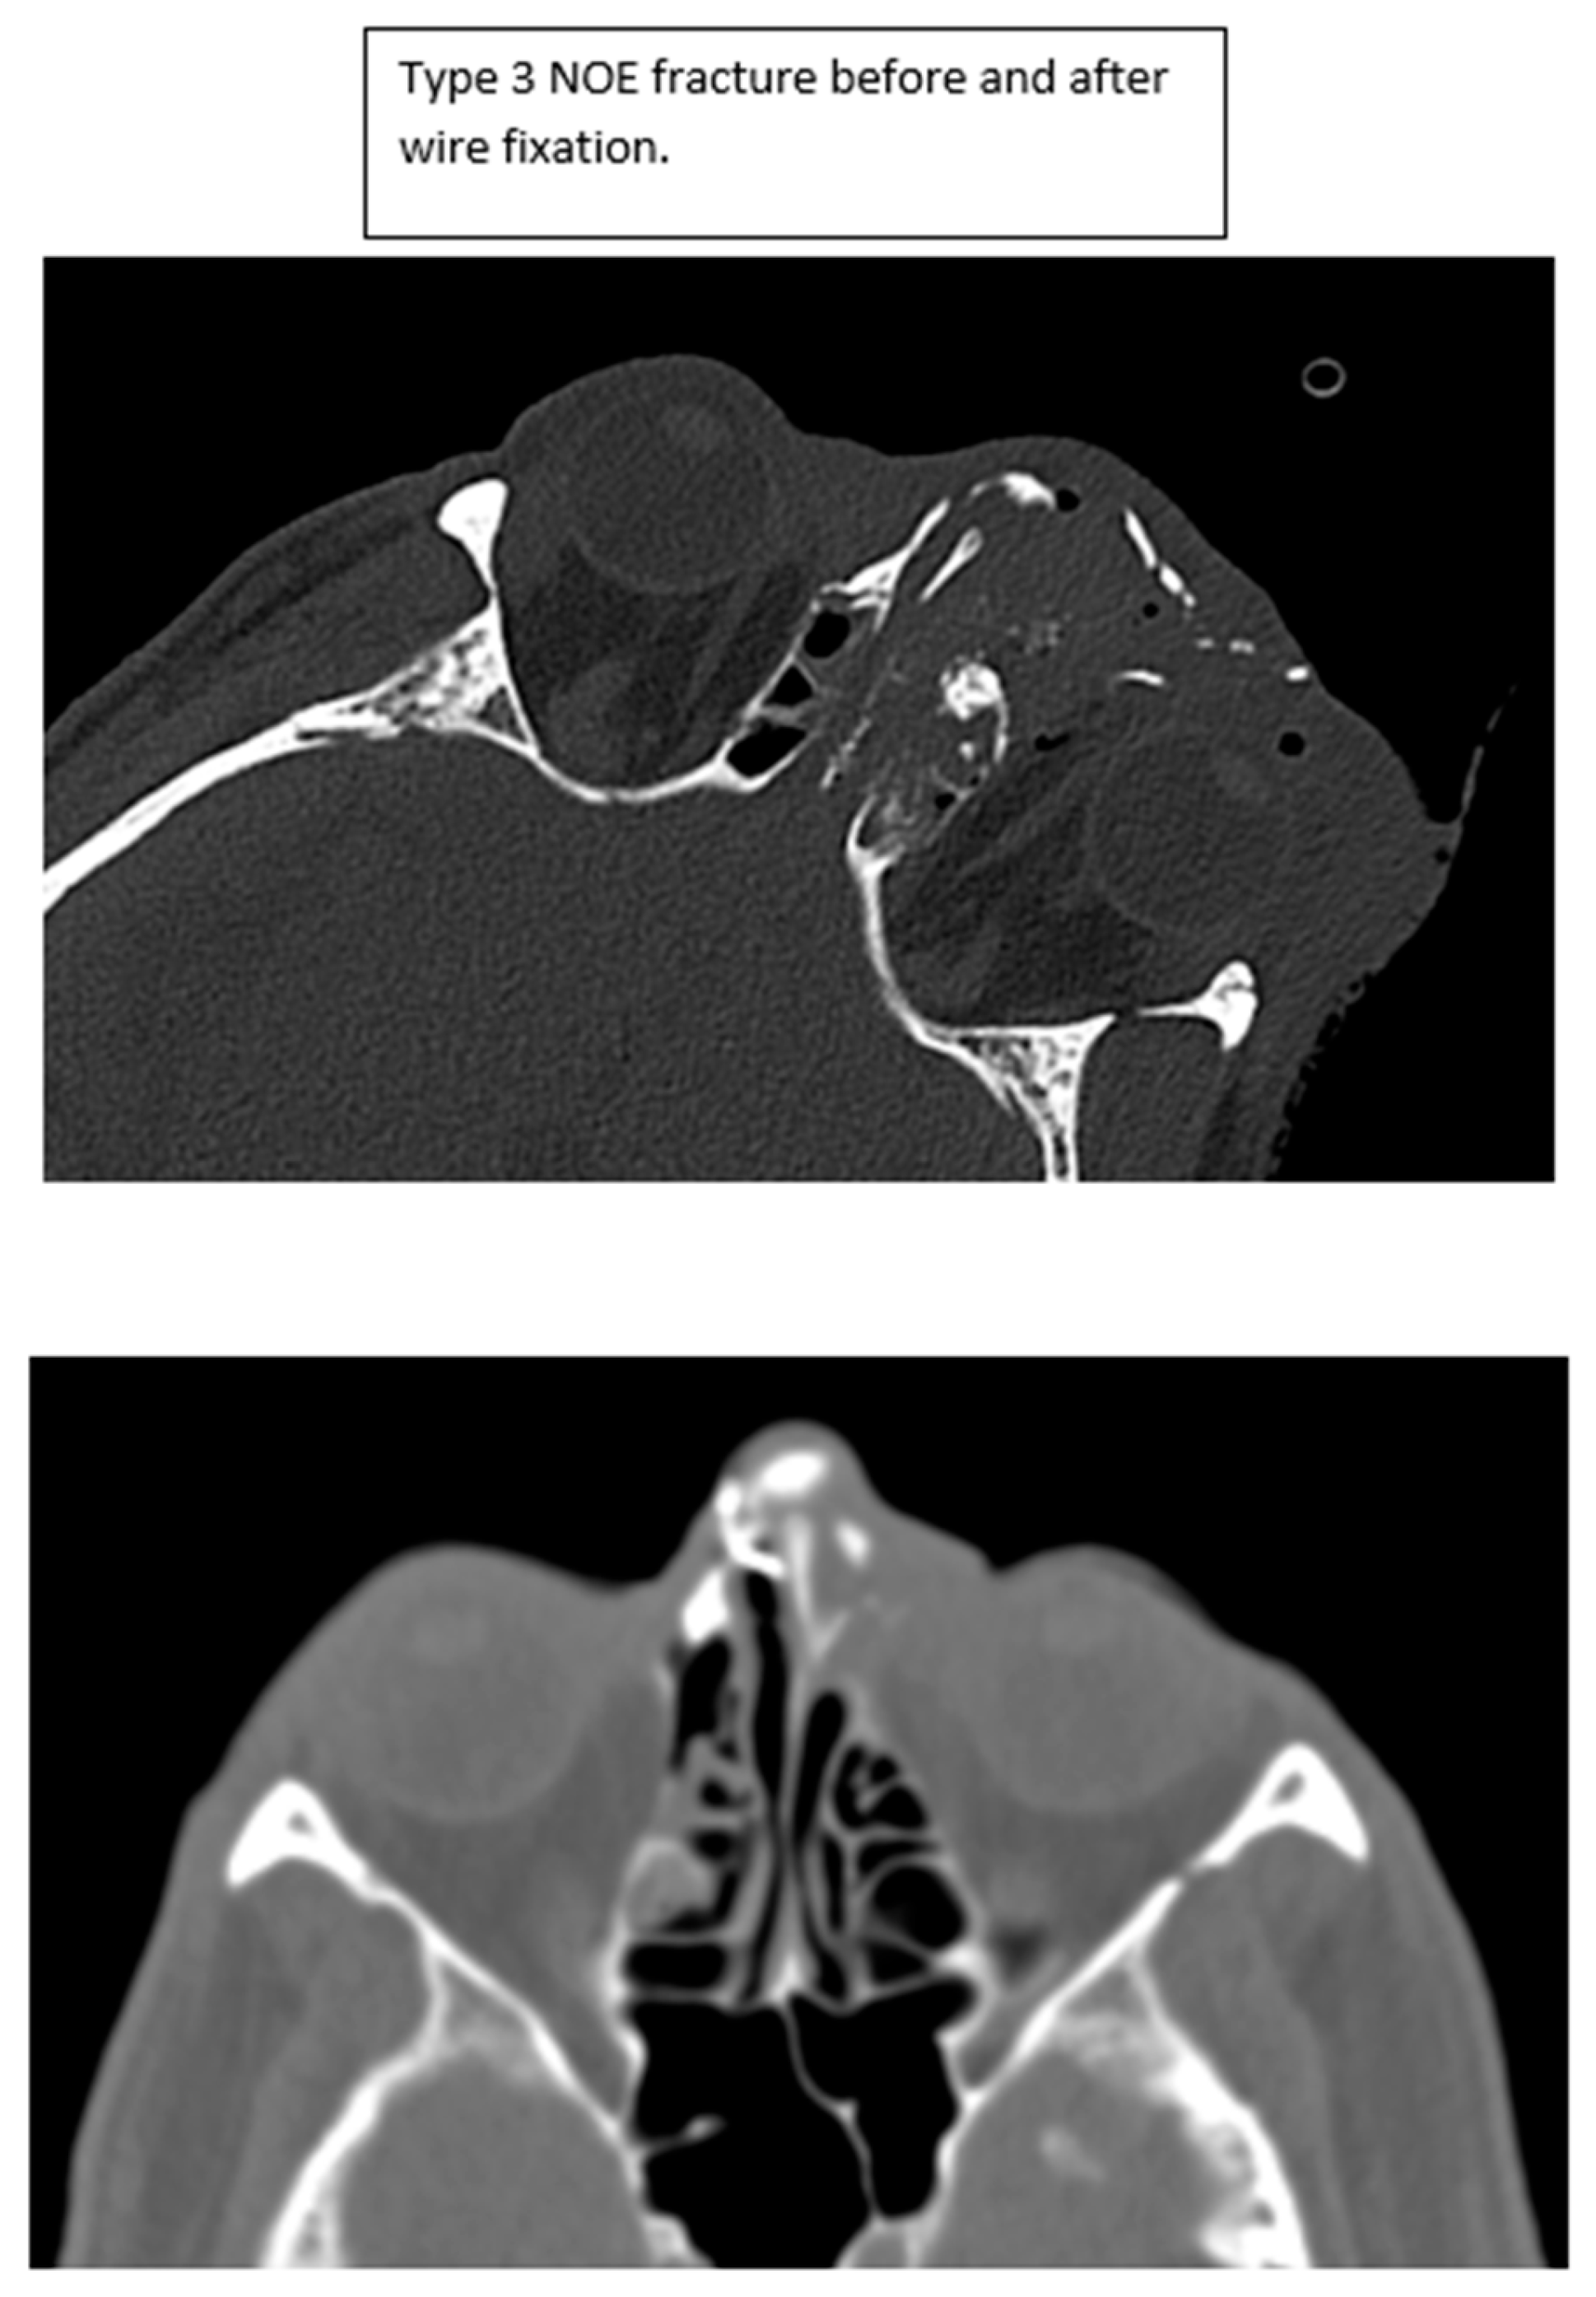

Figure 6. Type 3 NOE fracture CT imaging before and after plate fixation.